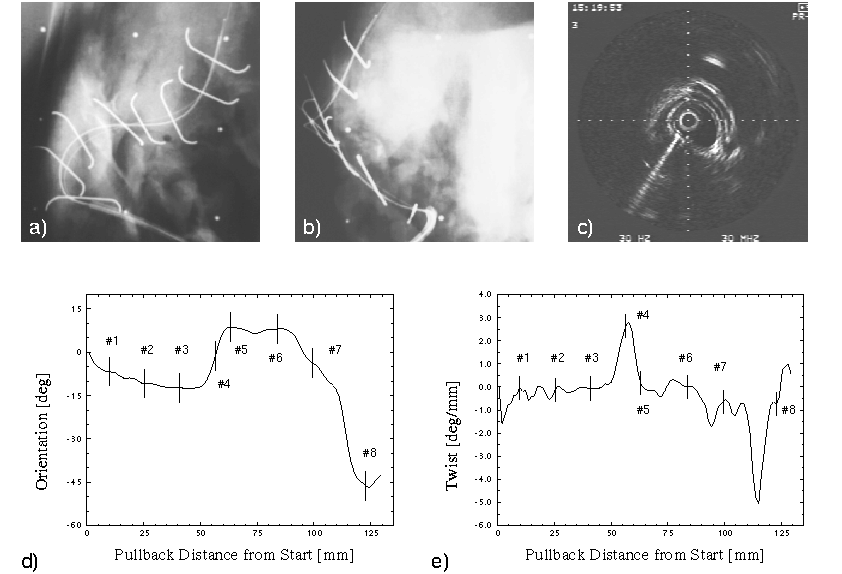

Preliminary Results of Validation using Metal Clips